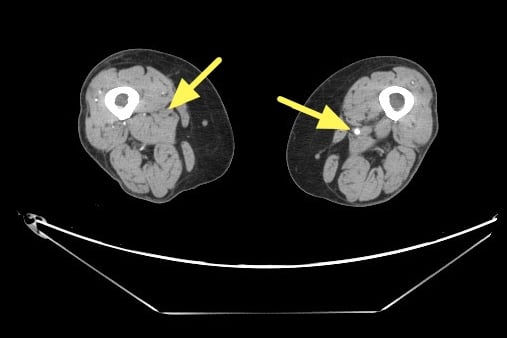

電腦斷層血管攝影顯示右股動脈脈阻塞(左側箭號處)。圖:聯新國際醫院提供

楊凱迪近期診治一位64歲長期洗腎的女性患者,數月來反覆出現下肢刺痛,夜深與洗腎後特別明顯,同時右小腿與腳踝各有一處約3x5公分久未癒合的慢性傷口。整形外科醫師清創時發現傷口幾乎沒有出血,轉介心臟血管外科,經「踝臂血壓指數(ABI)檢查」左右腳分別為僅約0.67及0.64,代表下肢血流循環不良。電腦斷層血管攝影更顯示雙側股動脈及膕動脈嚴重狹窄。